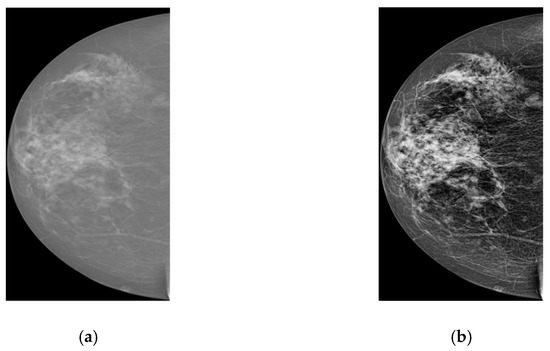

In the previous subsections, we discussed the overall flow of the proposed deep learning method from RoI generation, to improving classification accuracy of the object detection model with the help of a CNN-based classifier. All procedures are firstly performed on our private dataset as it has more and higher quality mammograms. Using the pre-trained model, we aim to fine-tune the network parameters for the INbreast database. However, before starting training on this dataset, some pre-processing procedures should be done. Firstly, two datasets contain mammograms with different intensities and contrast. Figure 4 shows two samples from each database for reference. In order to reduce the dataset difference for more accurate adoption, we enhance the texture and contrast (e.g., using CLAHE [29]) of INbreast mammograms. These pre-processing steps take place after breast region extraction but before square patch generation. Figure 5 shows samples before and after pre-processing operations. As seen from Figure 5b, the enhanced image now displays clear tissue information and is quite similar to mammograms in our private dataset.

Figure 4. Sample mammograms from two datasets: (a) RCC, (b) LMLO from our dataset and (c) RCC, (d) LMLO from the INbreast dataset.